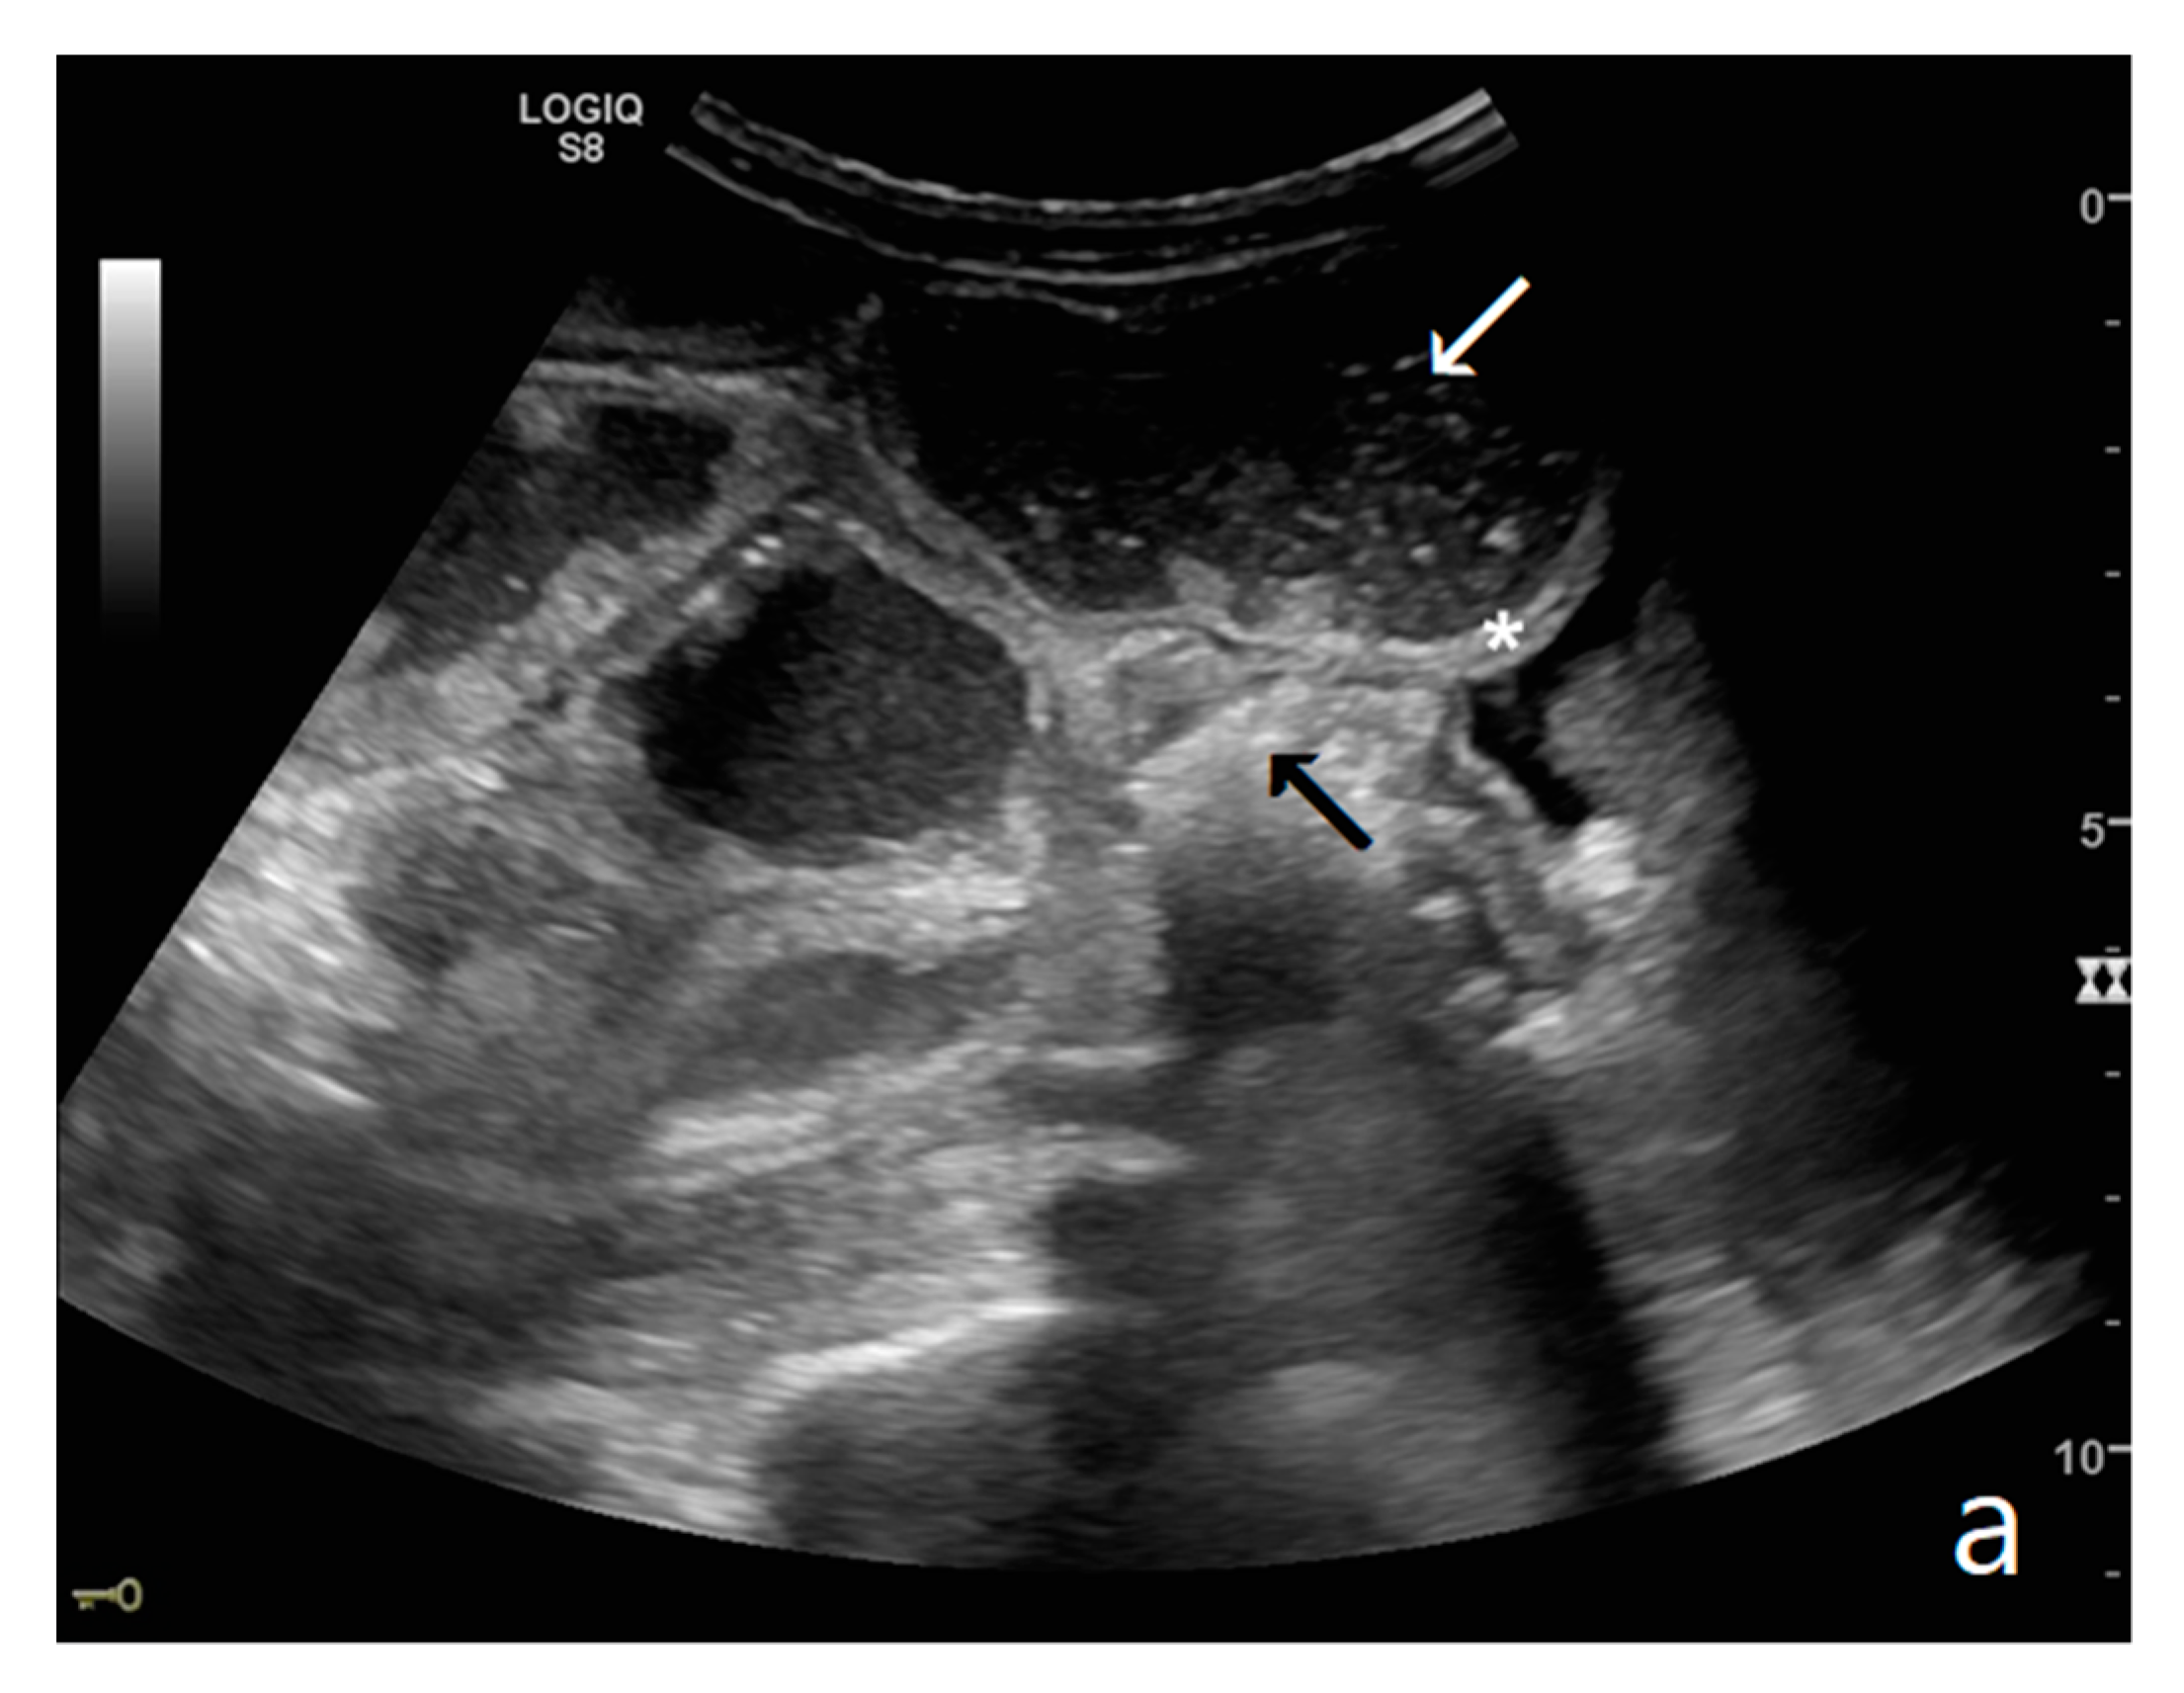

Figure 1.

(a,b). A simple SBO. Ultrasound images show fluid-filled, dilated small bowel loops (a,b) with hyper-kinesis and hyper-representation of valvulae conniventes (white arrow) (a); tail comet artifacts are visible due to air-fluid levels (dashed arrow) (b) and groups of bowel loops with severe differences in diameter (‘bowel jump diameter’) are evident more superficially (*) (b). No free fluid was detected in the abdominal cavity or between bowel loops.

Small bowel dilatation is defined as bowel diameter ≥2.5 cm measured from outer wall to outer wall [12,35,37]. At an early stage of the disease, the diameter should not be considered an absolute criterion for diagnosis, and other signs must be used: the bowel loop diameter at this stage could be within the normal range, but bowel loops are fluid-filled, hyperkinetic, and with plicar hyper-representation (Figure 1a and Figure 2a) [12].

Peristalsis alteration represents a fundamental criterion for the diagnosis of mechanical ileus [23]. In an emergency setting, there is no numerical nor quantitative parameter to evaluate kinesis, and although the evaluation is subjective, the method appears to have excellent diagnostic accuracy [12,31,38]. The kinesis can be reduced; ineffective, with a back-and-forth motion; or completely absent. Two important notes regarding the evaluation of peristalsis must be highlighted: the first, already mentioned above, concerns the ileum in the early stage in which the upstream bowel loop may appear hyperkinetic. A simple ileus at an early stage may not be easy to diagnose and requires adequate training, but evidence of fluid stasis, hyperkinesis, and a mildly dilated bowel loop can increase diagnostic confidence. Another important note concerning the evaluation of bowel kinesis is the possible error in interpreting false bowel movements due to the transmission of diaphragm breathing excursion; in this case, the false bowel movement appears to be synchronous with breathing events. In summary, bowel kinesis can be increased when SBO is in the initial phase but is reduced, ineffective, or absent in decompensated and complicated ileus. In the case of the absence of peristalsis, the bowel loop is defined as akinetic. In ultrasound evaluation, evidence of groups of bowel loops with different kinesis and diameter (loops proximal to the obstruction or downstream) increases diagnostic confidence (bowel jump kinesis) [12].